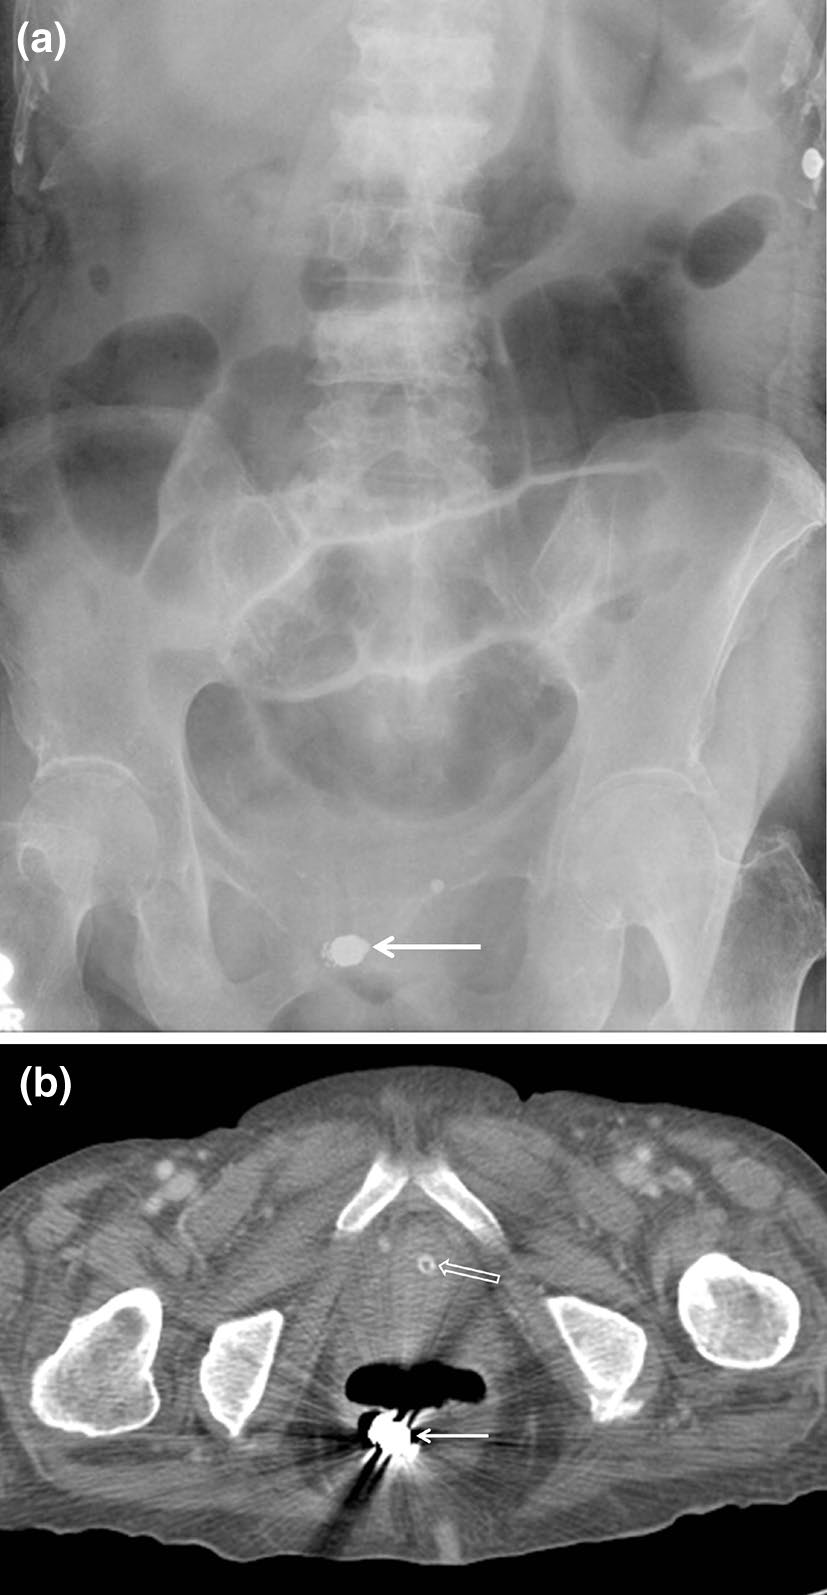

宫内节育器

宫内节育器(IUDs)是常用且高效的临时避孕装置,应位于子宫内膜腔中央。然而,它们可能在子宫腔内移位,远端脱入阴道,或通过子宫穿孔进入腹腔(图10)[2]。